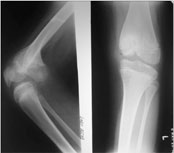

These are the x-ray pictures of the knee joint.

The picture on left is a lateral view of knee joint. While the tibia is seen in true profile the distal femur appears oblique.

The picture on the right is the antero-posterior view of the knee joint. The tibia is seen as frontal, the distal femur appears oblique. |